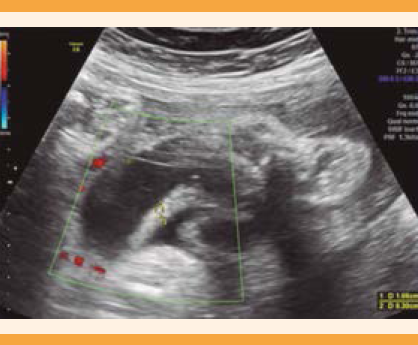

La medición del asa intestinal fue intra o extra abdominal en el área con mayor dilatación. (Figura 1) Las ecografías las tomaron obstetras con adiestramiento en Medicina materno fetal con un ultrasonido Voluson E8. Todos los embarazos finalizaron por cesárea, como protocolo del hospital a las 37 semanas, independientemente de la dilatación intestinal, a menos que hubieran comenzado con trabajo de parto, alteración de la flujometría Doppler o datos de estado fetal incierto. Al momento de finalizar el embarazo se programó la cesárea y se dispuso de otro quirófano, preparado para efectuar inmediatamente el cierre primario en el neonato.

Figura 4 Relación entre la dilatación del asa intestinal y el tipo de cierre de la pared abdominal al nacimiento.